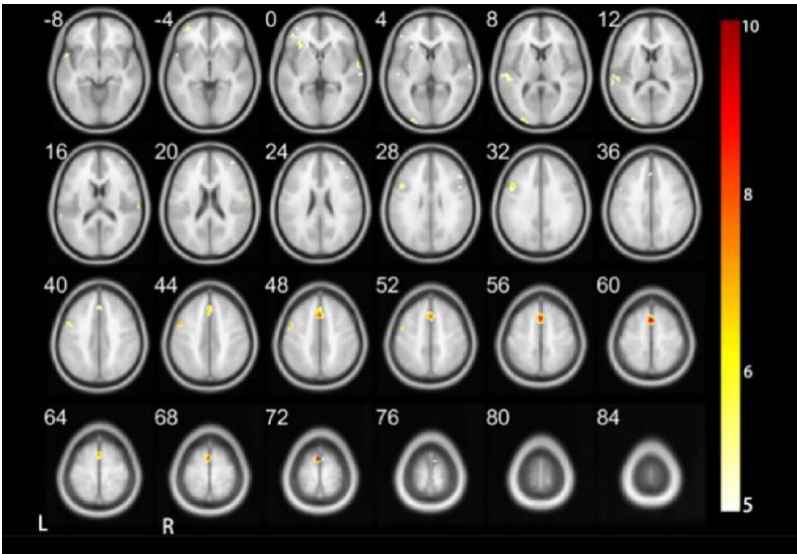

跨模态神经通路的重构

在四声识别时,聋儿童显著激活左半球颞中回(视觉信息处理)和右半球颞上回("沉默听觉网络"残余功能),而正常儿童则依赖右半球小脑Crus1(运动协调)和内侧顶叶(多感官整合)。这种神经通路的重构表明,聋儿童通过视觉-听觉跨模态重组建立新的信息处理路径。

半球偏侧化的语言特异性

最具启示性的发现出现在三声任务中:聋儿童呈现右半球优势激活(右侧岛叶和额中回),而正常儿童表现为经典左半球语言区主导。这种反转模式暗示,汉语声调在聋儿童大脑中可能被重新归类为"非语言性声学特征",通过右半球进行非典型处理。